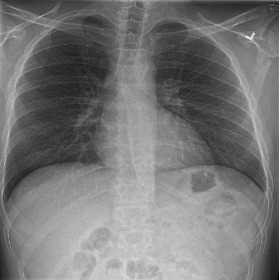

Fig. 3 shows image samples from the above datasets.

Figure 3: Image diversity across four datasets: (a) JSRT, (b) Montgomery County X-ray, (c) NIH ChestX-ray14, and (d) CheXpert